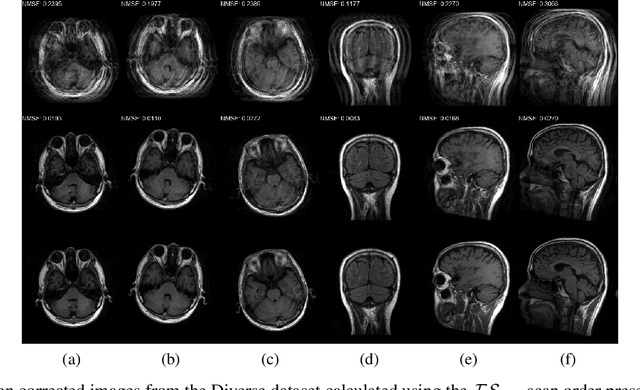

Abstract:Motion artefacts created by patient motion during an MRI scan occur frequently in practice, often rendering the scans clinically unusable and requiring a re-scan. While many methods have been employed to ameliorate the effects of patient motion, these often fall short in practice. In this paper we propose a novel method for removing motion artefacts using a deep neural network with two input branches that discriminates between patient poses using the motion's timing. The first branch receives a subset of the $k$-space data collected during a single patient pose, and the second branch receives the remaining part of the collected $k$-space data. The proposed method can be applied to artefacts generated by multiple movements of the patient. Furthermore, it can be used to correct motion for the case where $k$-space has been under-sampled, to shorten the scan time, as is common when using methods such as parallel imaging or compressed sensing. Experimental results on both simulated and real MRI data show the efficacy of our approach.